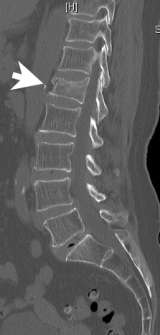

Compression fracture of the vertebral body is common. It is defined as a vertebral bone in the spine that has decreased in height by at least 15% due to the fracture (Figure 1). It is more common in the lower spine (thoracic and lumbar). Some vertebral compression fractures may heal on their own. However, in most cases, the compressed vertebrae do not fully heal since the fractured vertebral fragments continue to move even with a back brace.